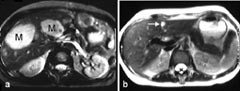

De aller fleste kontrastmidler som benyttes ved MR, er paramagnetiske (hvilket betyr at molekylene i kontrastmidlet blir magnetiske når de bringes inn i det kraftige magnetfeltet i en magnettomograf). Paramagnetiske stoffer kan påvirke T1-relaksasjonen og/eller T2-relaksasjonen til hydrogenkjernene i omkringliggende vannmolekyler, og dermed påvirke signalstyrken både i T1-vektede og T2-vektede MR-bilder. Hittil har man mest benyttet vannløselige, ekstracellulære kontrastmidler til intravenøs injeksjon. Disse fordeler seg i kroppen og utskilles helt analogt til de vanligste jodholdige røntgenkontrastmidlene. De viktigste indikasjonene er påvisning av tumor og inflammatoriske prosesser og bruk ved kontrastforsterket MR-angiografi (16), perfusjonsstudier og MR-artrografi. I de senere år har det imidlertid tilkommet mange nye kontrastmidler, og enda flere er under utvikling. Eksempler er leverspesifikke kontrastmidler som enten tas opp selektivt i hepatocyttene eller i kupffercellene (det retikuloendoteliale system) (fig 7), lymfespesifikke kontrastmidler (tas opp i lymfeknuter), intravaskulære kontrastmidler som holder seg i blodbanen (spesielt for MR-angiografi og perfusjon) og tumorspesifikke kontrastmidler (foreløpig på eksperimentstadiet). Det arbeides også med såkalte hyperpolariserte gasser, som er magnetiserte edelgasser (xenon, helium). Disse kan bl.a. utnyttes til MR-avbildning av bronkialtre og lunger, med en detaljoppløsning som langt overgår scintigrafi.